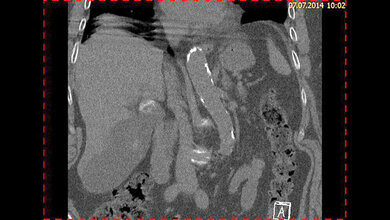

Der Pharmazeutin ist es jetzt gelungen, die Protein-Gruppe auch im Gallenblasenkrebs zu überführen. „Wir konnten die Proteine in zahlreichen Gewebeproben von Gallenblasenkrebs-Patienten nachweisen. Außerdem konnten wir zeigen, dass der Tumor schneller wächst, wenn die Zellen viel an Protein IMP2 enthalten. Auch die Prognose für den Patienten fällt in diesem Fall schlechter aus“, erklärt die Forscherin.

Bei ihrer Forschung arbeitete Sonja Keßler mit dem Magdeburger Pathologen Professor Johannes Haybäck zusammen: Haybäck hat die weltweit größte Sammlung an Gewebeproben von fast 500 Gallenblasenkrebs-Patienten aufgebaut. Mithilfe dieser Gewebebank konnte die Saarbrücker Pharmazeutin mit IMP2 erstmals einen vollkommen neuen Beteiligten am Gallenblasenkrebs identifizieren. Bei ihren Experimenten hat sie die IMP-Proteine in den Gewebeproben mit Hilfe von markierten Antikörpern sichtbar gemacht und analysiert. (idw, red)